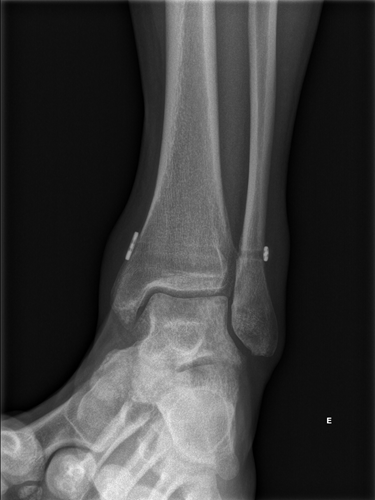

Geralmente a suspeita diagnóstica é confirmada com exames de imagem. A radiografa em carga pode logo ser confirmatória em lesões grosseiras. Em lesões mais subtis, é necessário a realização de ressonância magnética.

As lesões da sindesmose podem ser classificadas de acordo com a gravidade da lesão (número de ligamentos afetados), o grau de instabilidade do tornozelo e a diástase (separação) entre a tíbia e o peróneo nos exames de imagem.

• Lesão de Grau I (Leve): Estiramento ou rotura parcial dos ligamentos da sindesmose sem diástase entre a tíbia e o peróneo.

• Lesão de Grau II (Moderada): Rotura parcial com alguma diástase (na RMN e mas não no Rx), podendo haver sinais de instabilidade ou não, o que condiciona o tipo de tratamento.

• Lesão de Grau III (Grave): Rotura completa dos ligamentos da sindesmose com diástase clara entre a tíbia e a fíbula (já visível no Rx), resultando em instabilidade evidente do tornozelo.